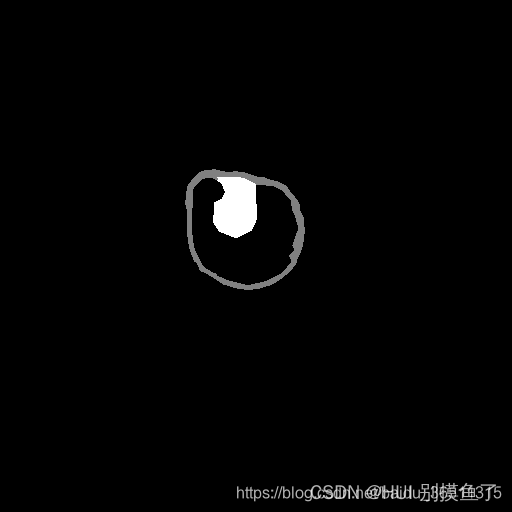

注:

-

灰度值:灰色128为膀胱内外壁,白色255为肿瘤。标签为 [0 128 255 ]。

-

任务:是要同时分割出膀胱内外壁和肿瘤部分,加上背景,最后构成一个三分类问题。